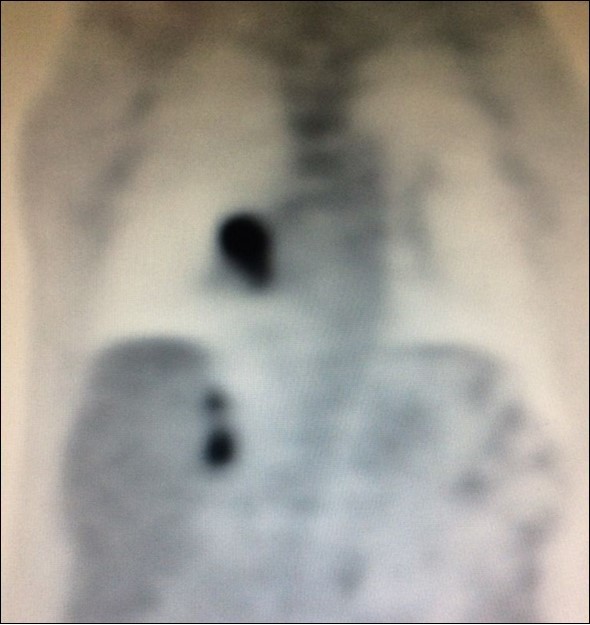

Nevertheless, in another study, only 28 out of 39 (71.8%) patients who underwent adrenalectomy for suspect adrenal tumor by FDG-PET/CT confirmed metastasis. Ten of those were benign adenoma and one was a non-functional pheochromocytoma29. Thus, FDG-PET/CT produced an unexpected high rate (28.2%) of false-positive results in this trial. Despite benign adenoma may mimicking metastasis and produce a positive preoperative FDG-PET/CT, history of primary lung malignancy and SUV max >2.65 were more commonly associated with metastasis in this paper (Figure 2).

Figure 2.PET-CT with high uptake on right adrenal